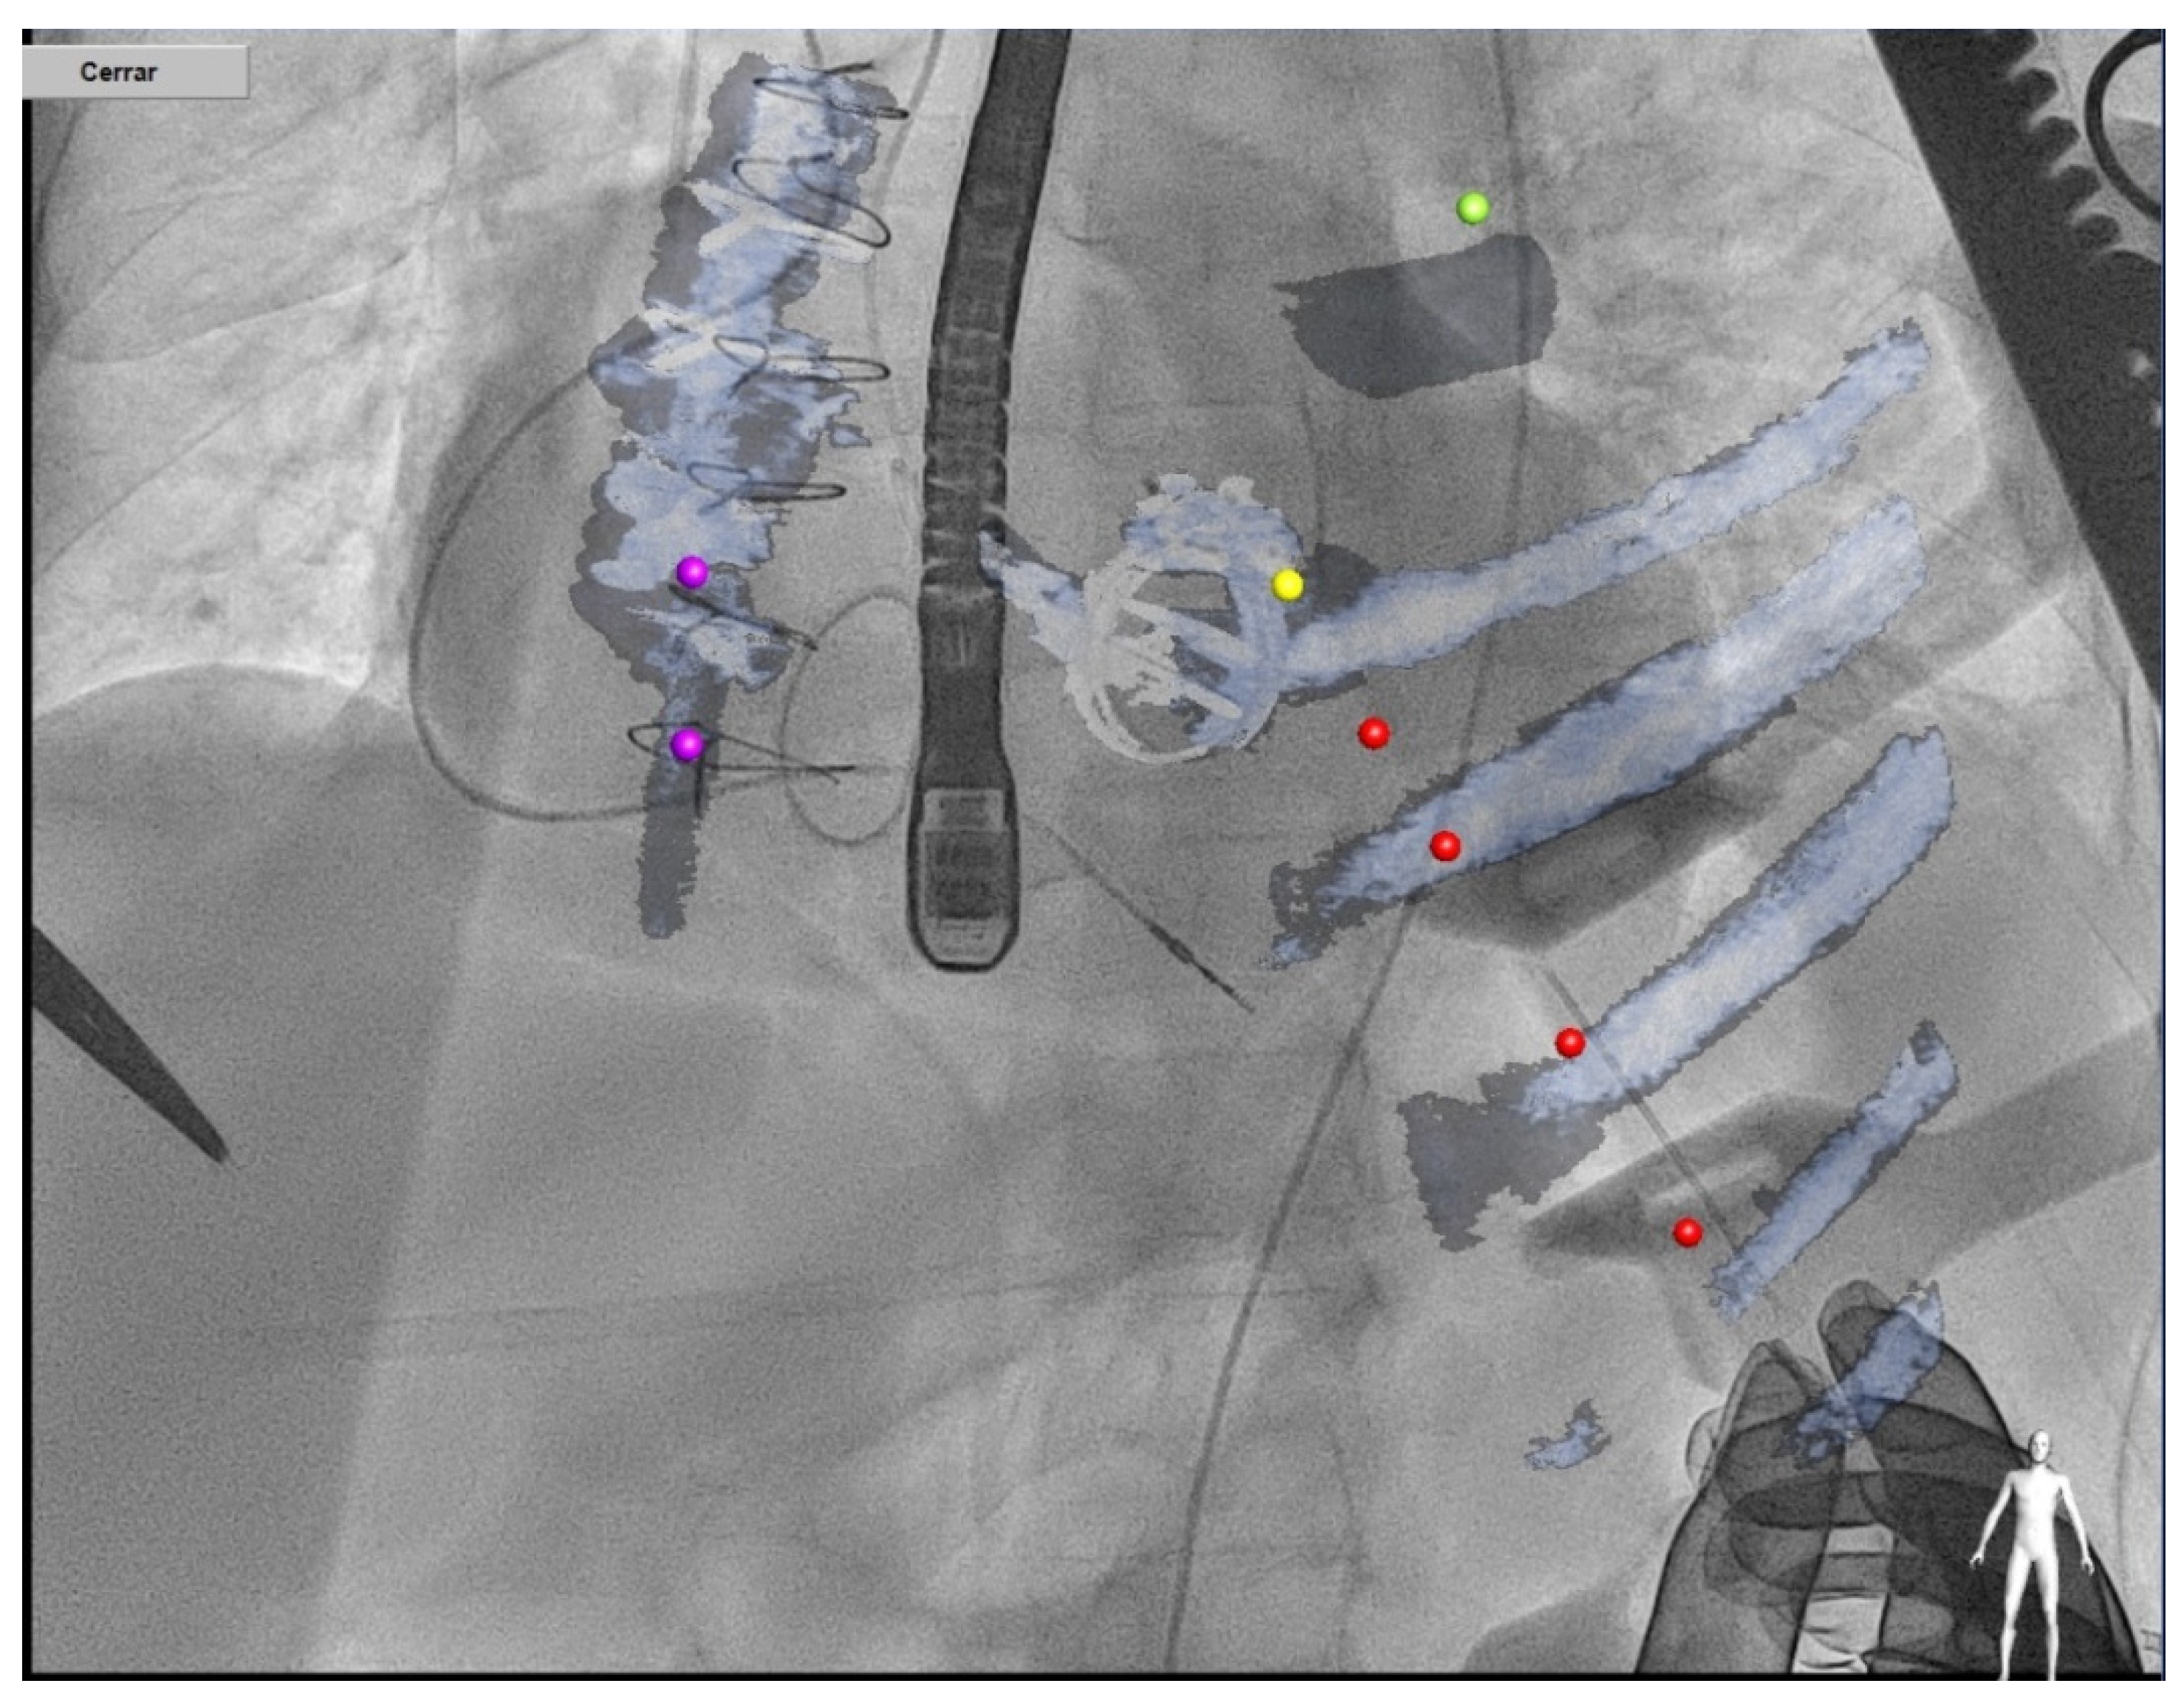

4.3. Procedure

4.3.1. Anterograde Approach